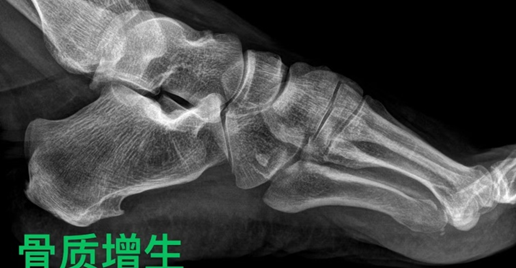

(8)骨质增生:通俗理解为骨刺,是一种自我修复的病理过程。往往沿着骨骼边缘生长,形成骨性突起。也称骨赘。中老年人常见。